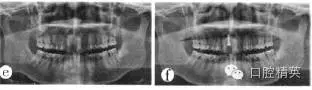

x線片輔助檢查示:右上中切牙牙根內(nèi)吸收明顯,根管內(nèi)徑大于根徑的1/2,根尖孔敞開,根尖有陰影,牙根長度短于對側(cè)同名牙(圖1a)。

圖1a牙根內(nèi)吸收;

(1)根管治療及冠修復(fù):開髓,拔髓,擴(kuò)大根管,根管消毒后行Vitapex糊劑+牙膠充填;X線片示:糊劑充滿根管達(dá)根尖,根充密實(shí)(圖1b)。觀察1個月無不適,完成烤瓷冠修復(fù)。

圖1b根充完成;

(2)拔除患牙:完成根管治療后約2.5年,患牙出現(xiàn)根尖區(qū)壓痛、牙齦瘺管。X線片顯示根充糊劑已吸收,根尖區(qū)根充物不夠密實(shí)(圖1c)。去除原根充物,多次換藥、消炎,重新根充。瘺管一直未閉,患者要求拔除。拔除后發(fā)現(xiàn):牙根內(nèi)吸收導(dǎo)致右上中切牙根管在根尖1/3的唇側(cè)穿孔,牙膠超充(圖1d)。由于x線片是二維成像,唇舌側(cè)影像重疊,不能及時發(fā)現(xiàn)超充物,引起根尖刺激癥狀,瘺管不閉。

圖1c根充物吸收;d拔除的患牙;